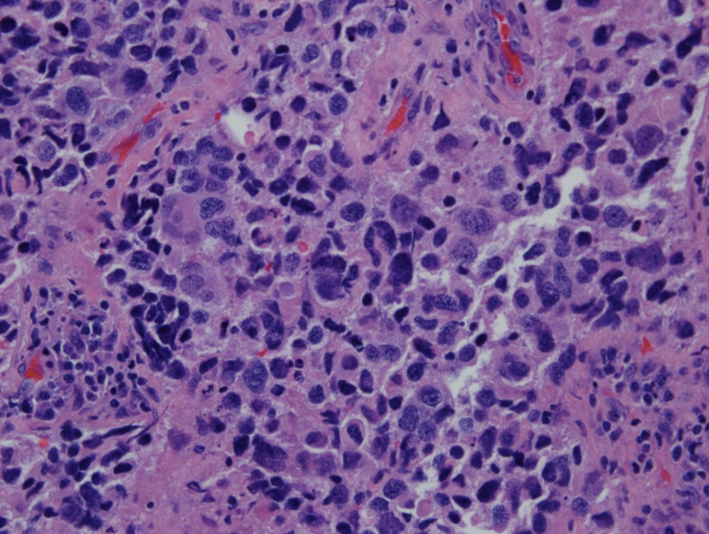

Pathologic examination of resected tumor showed large cells growing in sheets and nests (Fig. 3) There was numerous mitosis noted with abundant necrosis indicating a high-grade tumor (Fig. 4). Immunohistochemical stains performed show that malignant cells are strongly positive for cytokeratins CAM 5.2 (Fig. 5) and CK7 and negative for cytokeratin CK20. In addition, the malignant cells are strongly positive for synaptophysin and chromogranin (Fig. 6, 7), focally positive for TTF-1 (Fig. 8) and negative for PSA, HMB45 and GFAP. This was consistent with large cell neuroendocrine metastatic carcinoma with likely lung primary.

![]() Click for large image | Figure 4. H&E (× 40) showing numerous mitotic figures. |